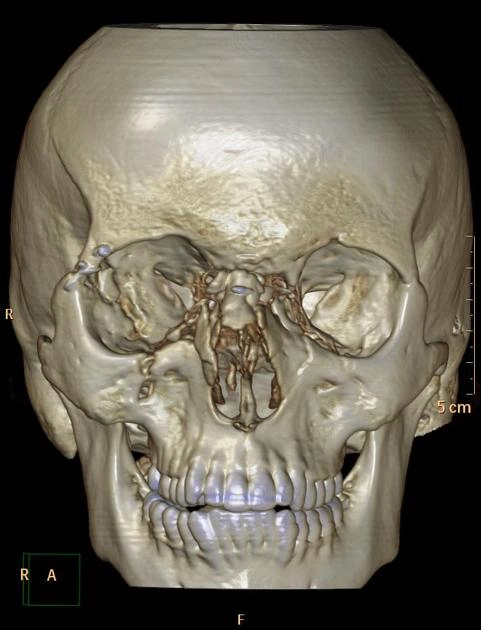

• Gãy xương phức tạp

Gãy xương Le Fort (Le Fort fracture classification)

Gãy phức hợp mũi sàng ổ mắt (Naso-orbitoethmoid (NOE) complex fracture)

Gãy hốc mắt "blow-out" (Orbital blow-out fracture)

Gãy phức hợp gò má - hàm trên (Zygomaticomaxillary complex fracture)